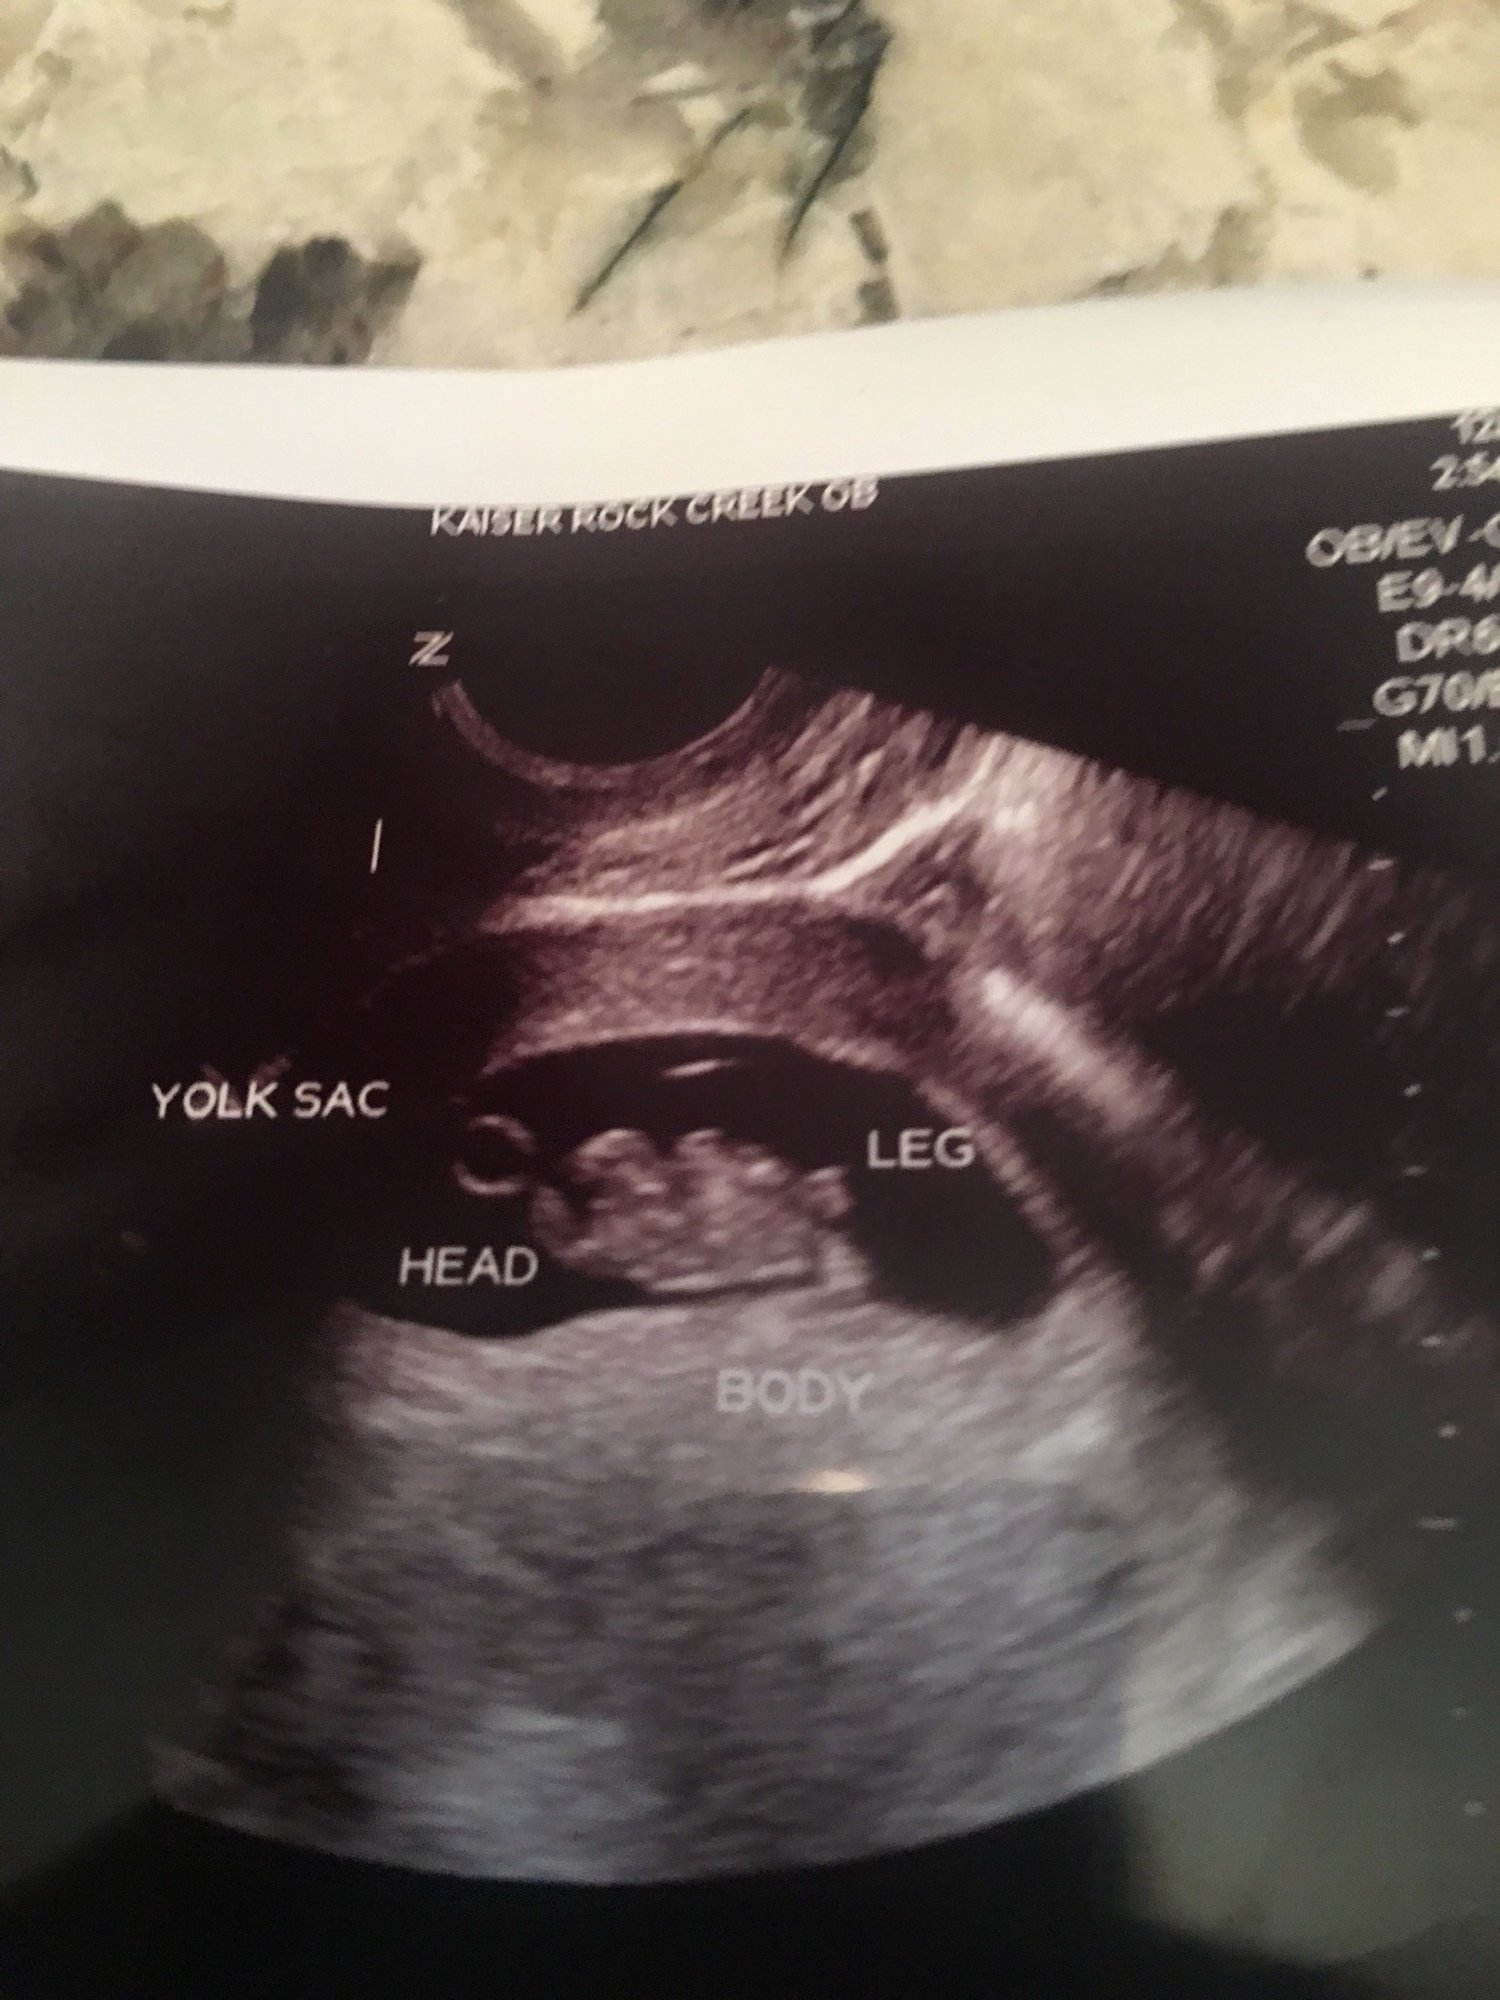

Ultrasound pic from this morning. Yolk sac and head are on the left and feet towards the right side of the picture. 9 weeks 1 day with a heartbeat of 171. This baby seemed chill compared to my last one who was flipping around like a little maniac during the first ultrasound.